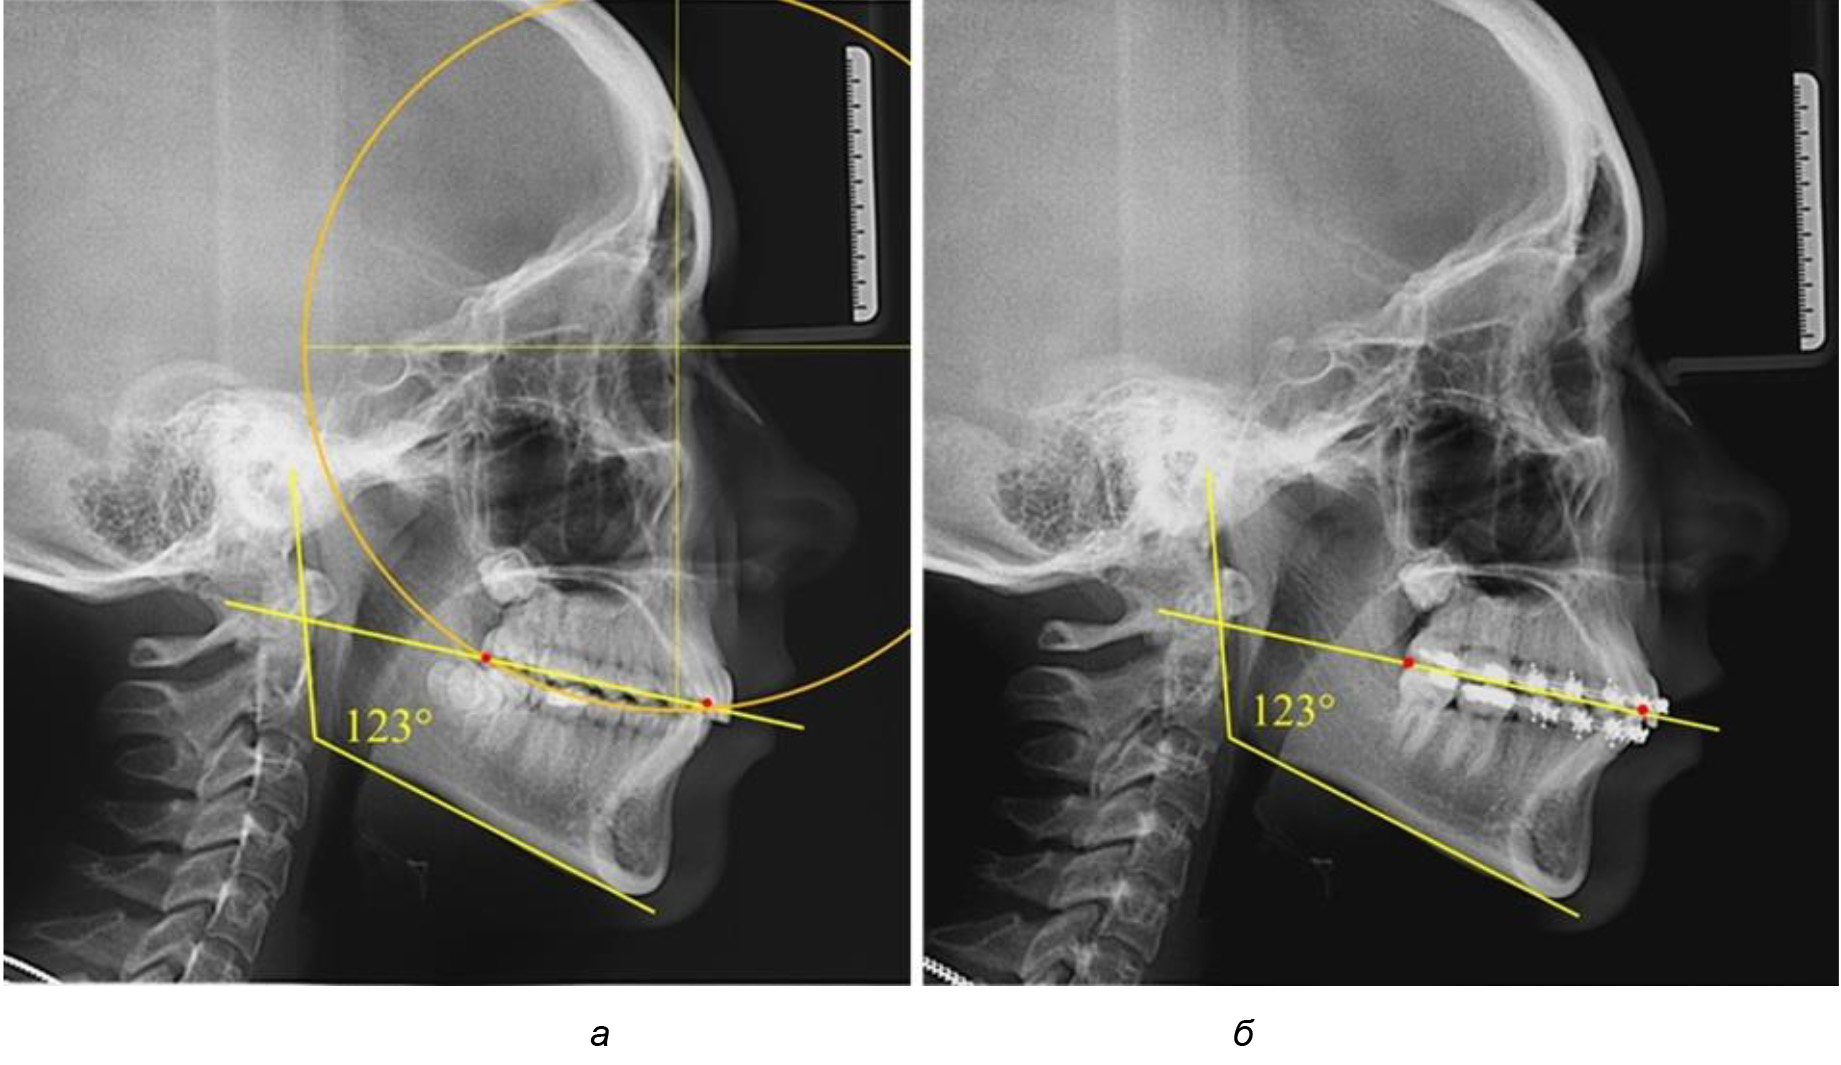

На рентгенограммах людей 2-й подгруппы (30 человек с нейтральным типом роста) величина угла нижней челюсти в среднем составила (120,34 ± 2,19) ° и характеризовала нейтральный тип нижней челюсти.

Глубина кривой Spee в среднем по 2-й подгруппе составил (3,54 ± 0,58) мм, что было незначительно меньше, чем при анализе аналогичного показателя 1-й подгруппы.

Достоверных различий с показателями, полученными при анализе ТРГ и ОПТГ, нами не отмечено (р ˃ 0,05). Деление величины радиуса круга к длине окклюзионной линии составило 1,612 ± 0,02, что, так же как и в 1-й подгруппе, было близким по значению к числу Фибоначчи (1, 618).

В 3-ю подгруппу вошли ТРГ и ОПТГ 14 человек 1-й группы, что составило (22,58 ± 5,31) % от общего количества людей 1-й группы. Величина угла нижней челюсти в среднем составила (114,85 ± 2,87)° и характеризовала горизонтальный тип нижней челюсти.

Глубина кривой Spee в среднем по 2-й подгруппе составил (2,94 ± 0,47) мм, что было меньше, чем в других подгруппах. Деление величины радиуса круга к длине окклюзионной линии составило 1,616 ± 0,02 (рис. 4).

Рис. 3. Особенности кривой Spee на ТРГ (а) и ОПТГ (б) при нейтральном типе роста нижней челюсти

Рис. 4. Особенности кривой Spee на ТРГ (а) и ОПТГ (б) у людей с горизонтальным типом лица